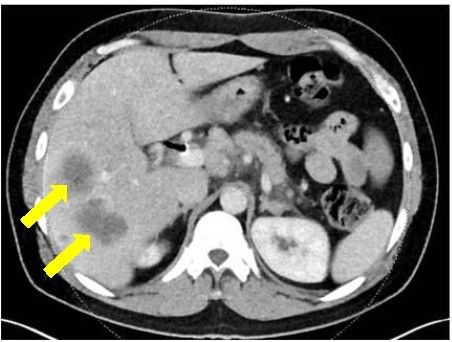

在2015年秋天,44岁的年轻人Doron Broman被诊断患有胰腺癌,生存期仅剩几个月。

确诊时

在接受最强的化疗方案FOLFIRINOX后,肿瘤虽然缩小,但是他无法承受强烈的副作用。他的主治医生,丹娜法伯癌症研究院的Kimmie Ng博士检测了Broman的肿瘤DNA的全部外显子序列,显示BRCA2基因的突变。他的医疗团队决定使用靶向Brac突变的药物,称为PARP抑制剂的olaparib(Lynparza) ,尽管这款药物当时仅获批用于卵巢癌。

在他使用奥拉帕尼六个月后,MRI和CT扫描显示没有癌症复发,生物标志物水平保持在正常范围。Ng说,只要癌症得到控制,他可以无限期地服用奥拉巴利,因为副作用很小。

FOLFIRINOX治疗5个月病灶明显缩小 vs olaparib治疗21个月病灶全部消失